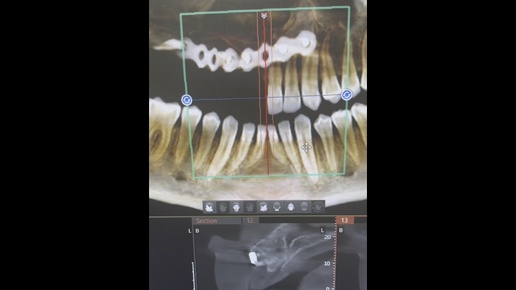

Сложный случай

Др. Суханов